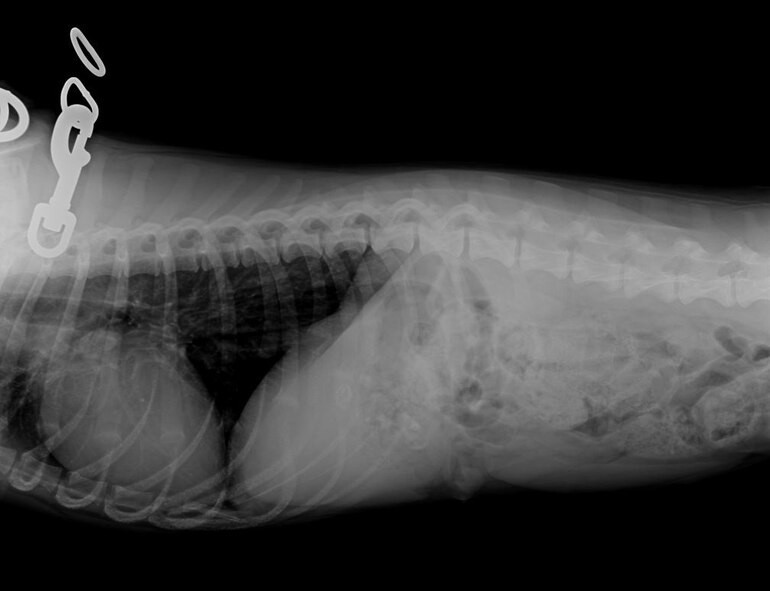

Dr. Darrin Olson, veterinarian, examines Grace, a 7 month old Bassador, for foreign objects lodged in her stomach, at the veterinary clinic, June 10, 2016. Animals with ingested foreign objects in their bodies generally do not feel well. They often stop eating and/or act depressed. (U.S. Air Force photo/Airman Alexis C. Frost)